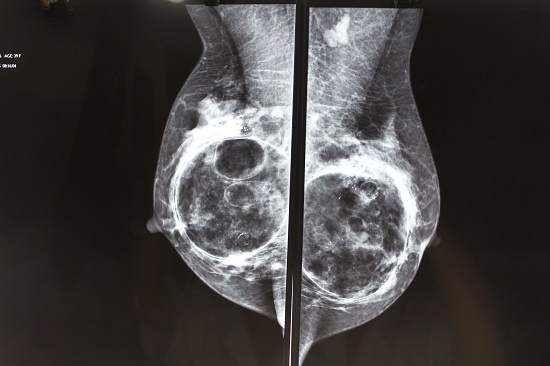

Tuyến vú bị biến dạng với các cục, khối do tiêm filler. Ảnh: Bác sĩ cung cấp

Trong đó, với các chị em, đa phần là các trường hợp mũi bị biến dạng, môi hoại tử, ngực nhiễm trùng, biến dạng tuyến sữa,… Nhiều trường hợp phải cắt bỏ hoàn toàn phần ngực và tái tạo bộ phận mới.